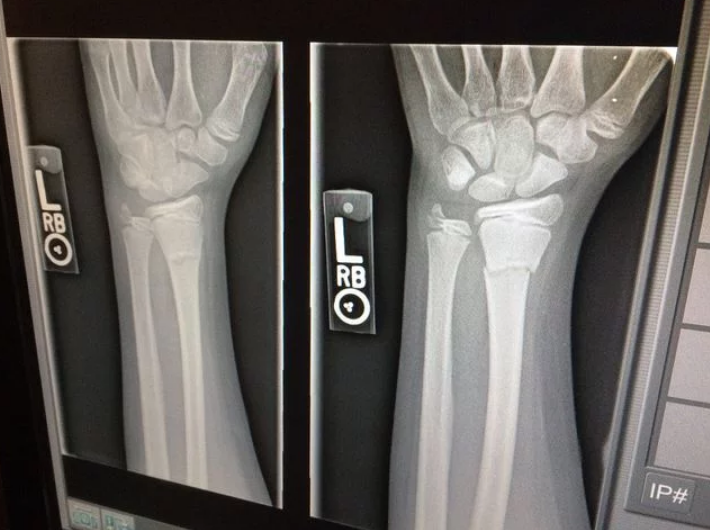

A 29-year-old inmate in a correctional center fell while in the recreation yard on November 19, 2016 and landed on his hand, hearing a loud popping sound. He immediately felt severe pain and his hand began...